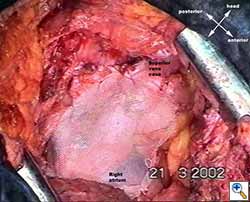

Medium and large-sized (Figures 1a, 1b) defects generally result after pneumonectomy for advanced central lung tumours which invade the pericardium (T3 invading pericardium), thus requiring reconstruction (Figure 1c). To achieve a curative resection, negative pericardial resection margins must be obtained and checked microscopically. More invasive tumours (T4 invading cardiac structures) require partial atrial resection and pericardiectomy associated with pneumonectomy.

| Figure 1c: Intraoperative aspect of pericardioplasty with Marlex mesh after right completion pneumonectomy with partial pericardiectomy. |

Video 1 depicts a pericardial reconstruction with Marlex after a right completion pneumonectomy with pericardiectomy for lung adenocarcinoma (see also Figure 1). The technique of pericardial reconstruction after the resection of invasive mediastinal tumours is illustrated in Figures 8a-c). Video 2 depicts a pericardial reconstruction with Mersilene mesh after the resection of a malignant thymoma invading the anterior pericardium (see also Figure 4b). The technique of right pericardial reconstruction after extrapleural pneumonectomy is illustrated in Figures 9a and 9b). Video 3 depicts a pericardial reconstruction using Gore-Tex Dual Mesh after a left extrapleural pneumonectomy (see also Figure 3). Care must be taken to prevent constriction (Figure 10).